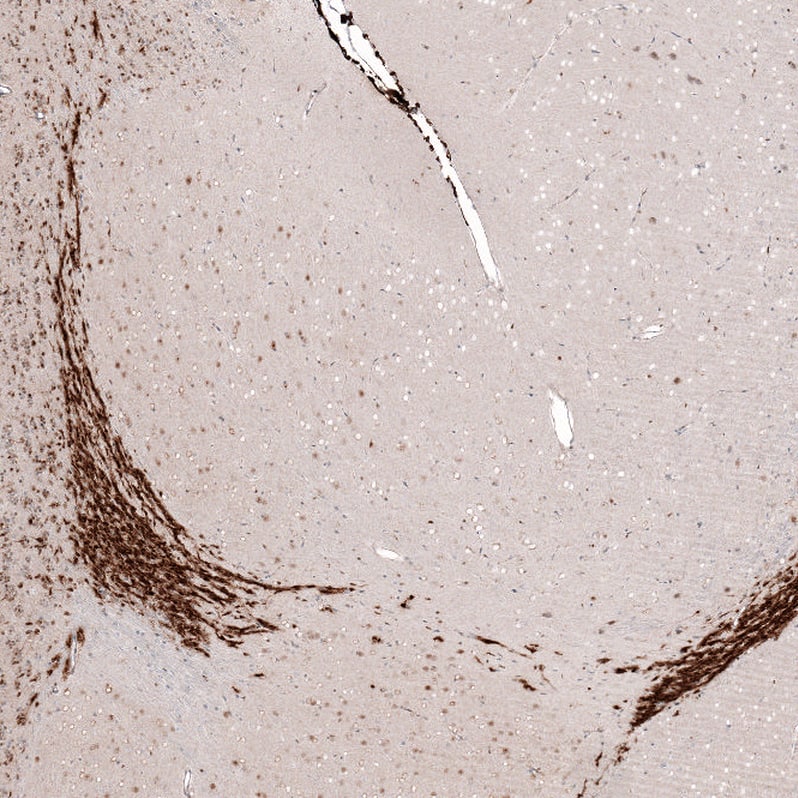

Immunohistochemistry-Paraffin: SOX4 Antibody [NBP3-44187]

Staining of human glioma shows moderate to strong nuclear positivity in tumor cells.Immunohistochemistry-Paraffin: SOX4 Antibody [NBP3-44187]